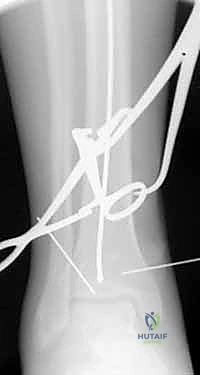

يبدأ التشخيص بالفحص السريري الدقيق لتقييم حالة الجلد، النبض، والأعصاب. يتبع ذلك إجراء الأشعة السينية (X-rays) من زوايا متعددة لتحديد موقع وشكل الكسر بدقة. في حالات الكسور المعقدة أو التي تمتد إلى مفصل الركبة أو الكاحل، يطلب البروفيسور هطيف إجراء أشعة مقطعية (CT Scan) للحصول على صورة ثلاثية الأبعاد تساعد في التخطيط الجراحي الدقيق.

باستخدام جهاز الأشعة السينية المتحرك داخل غرفة العمليات (C-arm Fluoroscopy)، يتم سحب الساق وإعادتها لوضعها التشريحي الصحيح (Reduction) دون فتح منطقة الكسر.

بعد ذلك، يتم إدخال سلك دليلي معدني رفيع داخل القناة النخاعية، يليه استخدام أدوات توسيع دقيقة (Reamers) لتنظيف وتوسيع القناة وتجهيزها لاستقبال المسمار. هذه الخطوة بحد ذاتها تحفز نمو العظم من خلال نشر الخلايا العظمية داخل القناة.